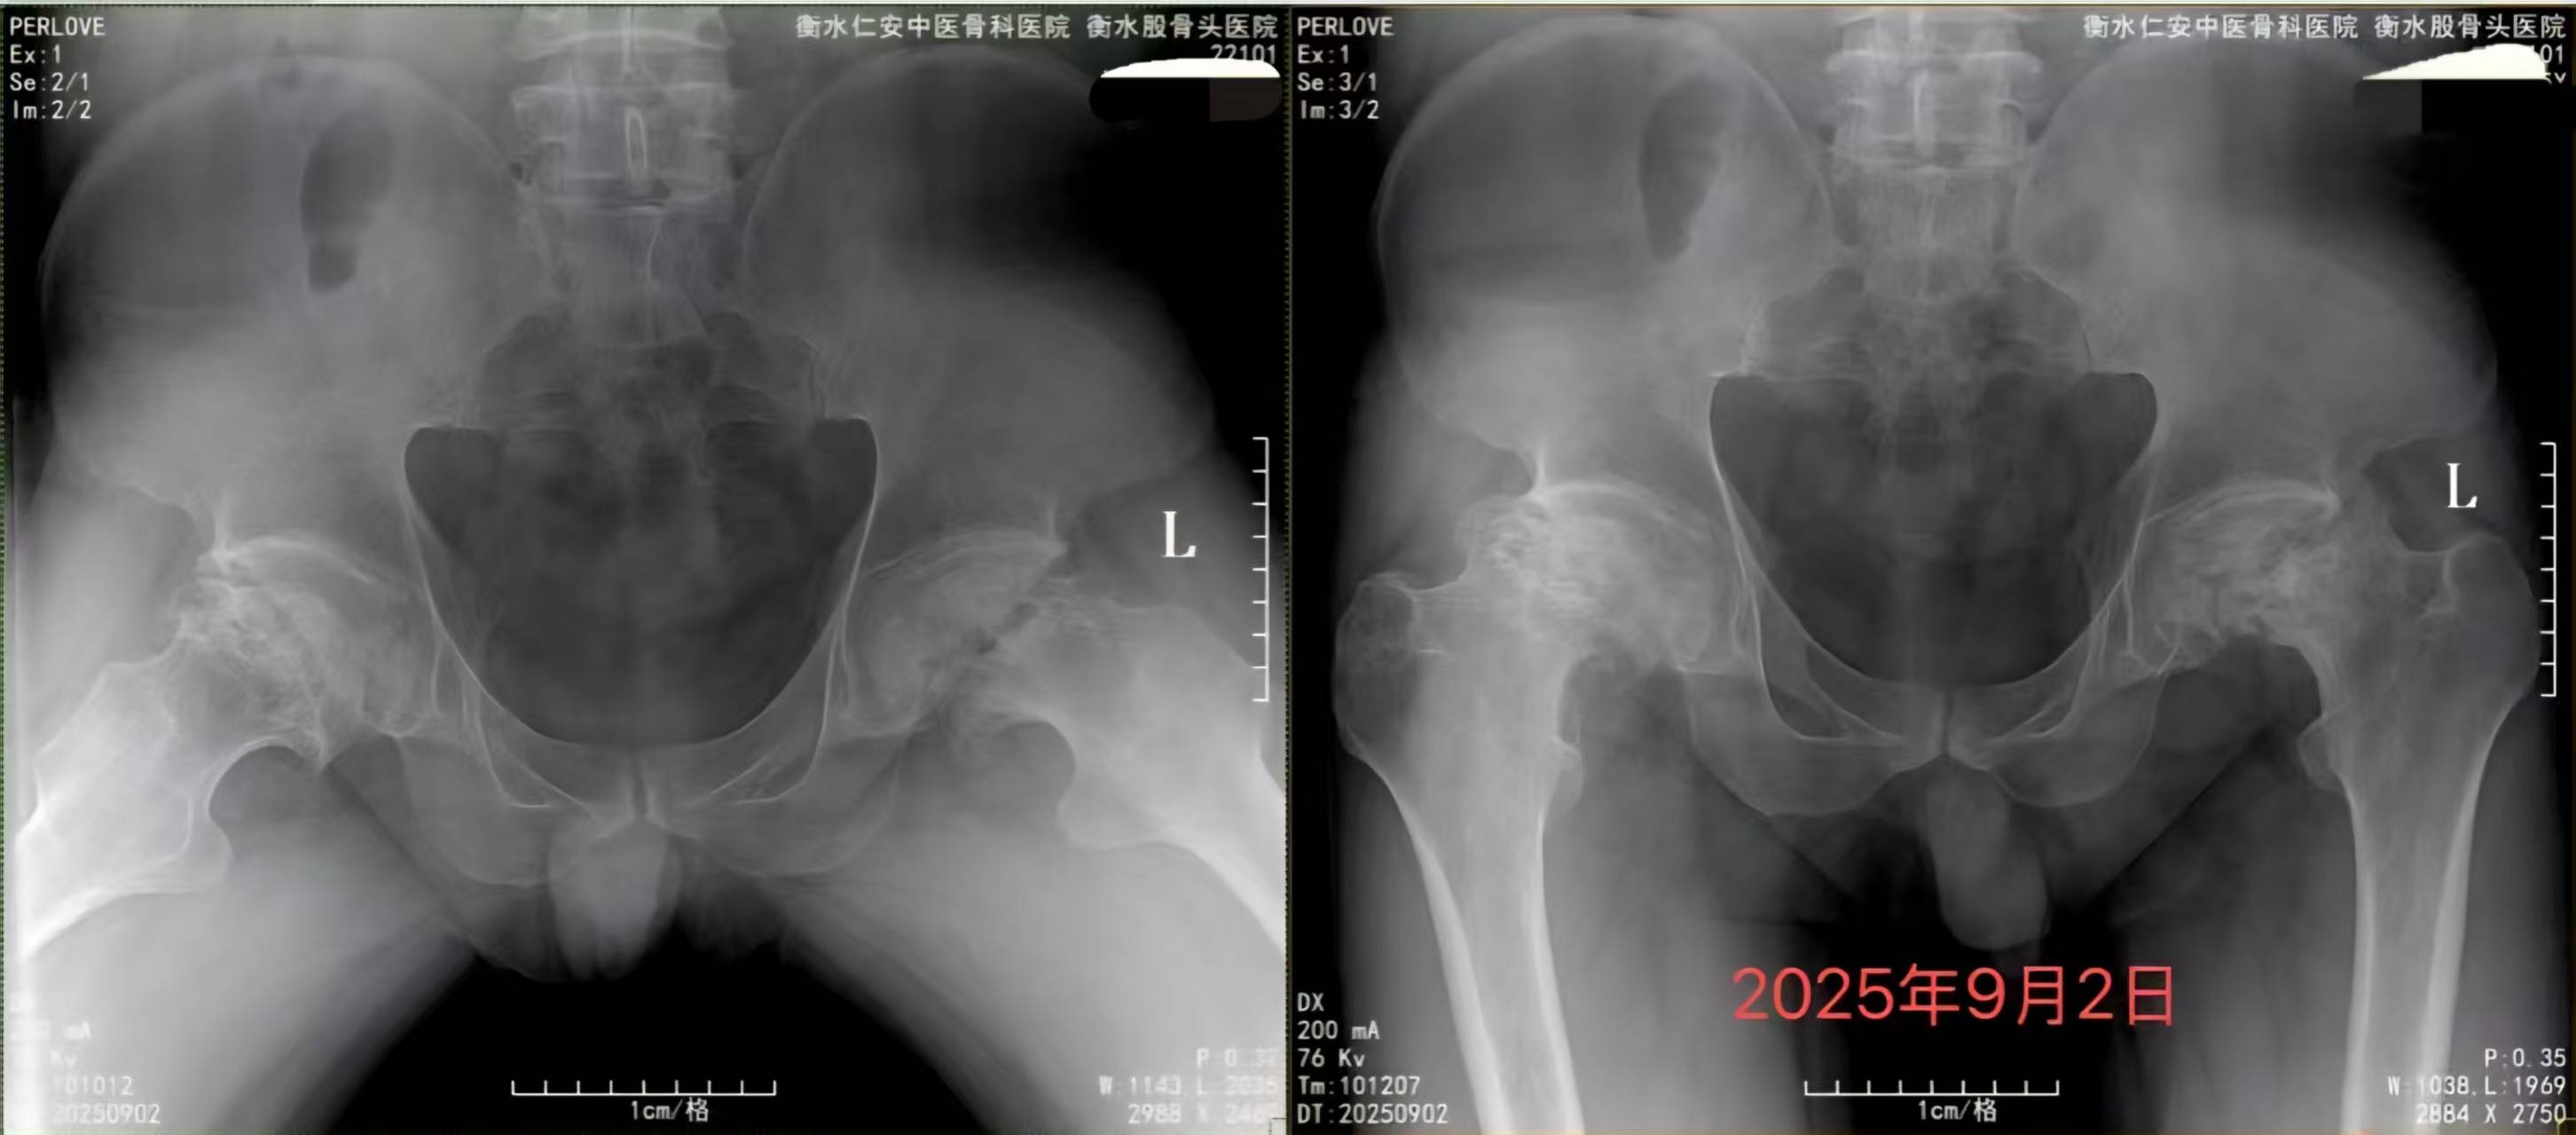

要维持髋关节灵活度,关键在于日常防护。控制体重是首要任务,减轻身体对髋关节的额外负担。养成适度运动的习惯,比如游泳、骑自行车或散步,这些活动对关节冲击小,能增强周围肌肉力量,提供更好支撑。同时,避免长时间负重或进行高强度跳跃等可能损伤股骨头的活动。注意保暖,避免髋部受凉。戒烟限酒有助于维护良好的骨骼供血。对于存在风险因素的人群,如长期使用激素或有过髋部外伤史,更应提高警惕,建议定期检查,通过医生评估和必要的影像学检查(如X光或MRI)来监测股骨头健康状况,及早发现潜在问题。